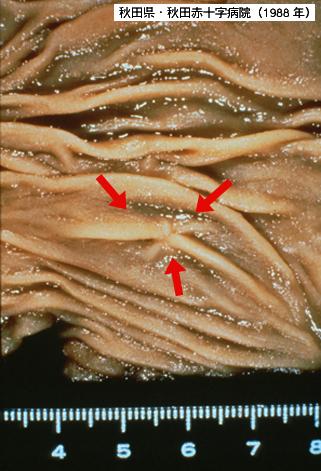

通过内窥镜发现的直径4毫米的表面凹陷型(IIc型)早期大肠癌

恶性上皮性肿瘤/腺癌

大肠/乙状结肠

切除标本(宏观)

0型(表在型)/IIc型(IIc)

1~9

sm